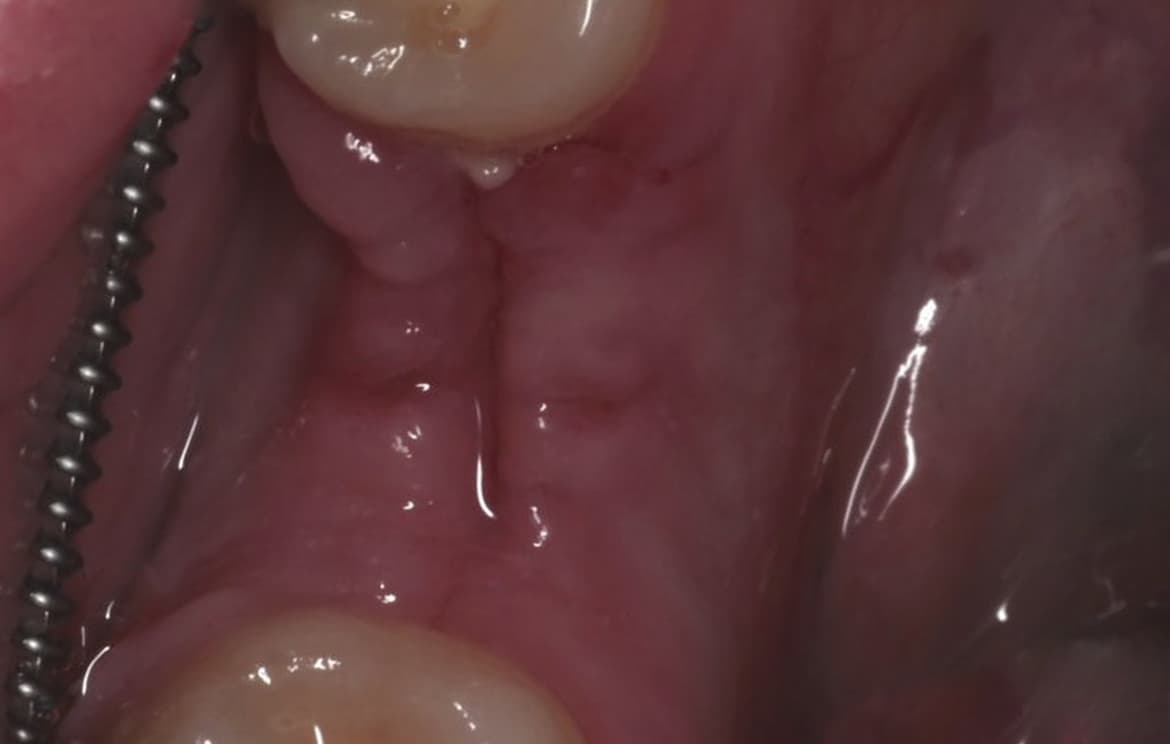

Наши работы